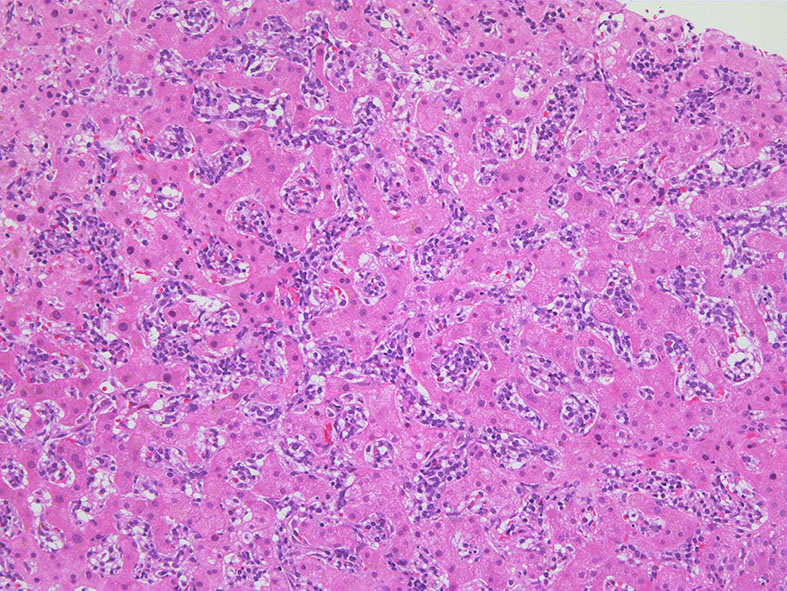

肝臓

肝針生検組織; 類洞に細胞浸潤が認められ, 非浸潤部との境界がぼんやりと認められる. 類洞と異なり, グリソン鞘は腫瘍細胞の浸潤が乏しいか, ほとんど認められない.

類洞内に浸潤増殖するリンパ腫細胞: 類円形・長円, 瓜状の核をもつ,細胞質の乏しい細胞(サムネイル画像のクリックで大きな画像が見られます)